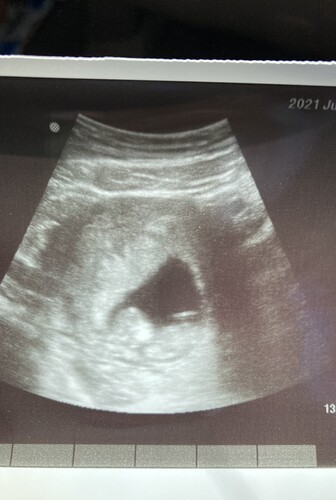

My bebe🥺 got a surprise ultrasound today at my appointment. The doctor said everything looked good and it was moving around like crazy!!! Looks like it already wants out lol

I told my husband it has his profile but he told me it has a giant head like me LOL